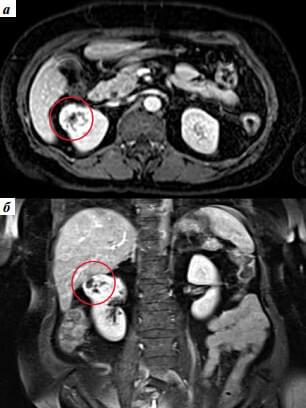

Drugi slučaj vezan je sa cistom prečnika 3 cm.

Bolest obično prolazi bez simptoma. Ne boli, nalazi su dobri, mokrenje se odvija bez problema.

Zato je cista bila tako velikog obima.

Devojka od 22 godine se bojala operacije. Propisali smo joj

Nefro Aktiv

. Za mesec dana, ponovljeni pregled nije pokazao nikakvu patologiju.

pre

pre

posle

posle